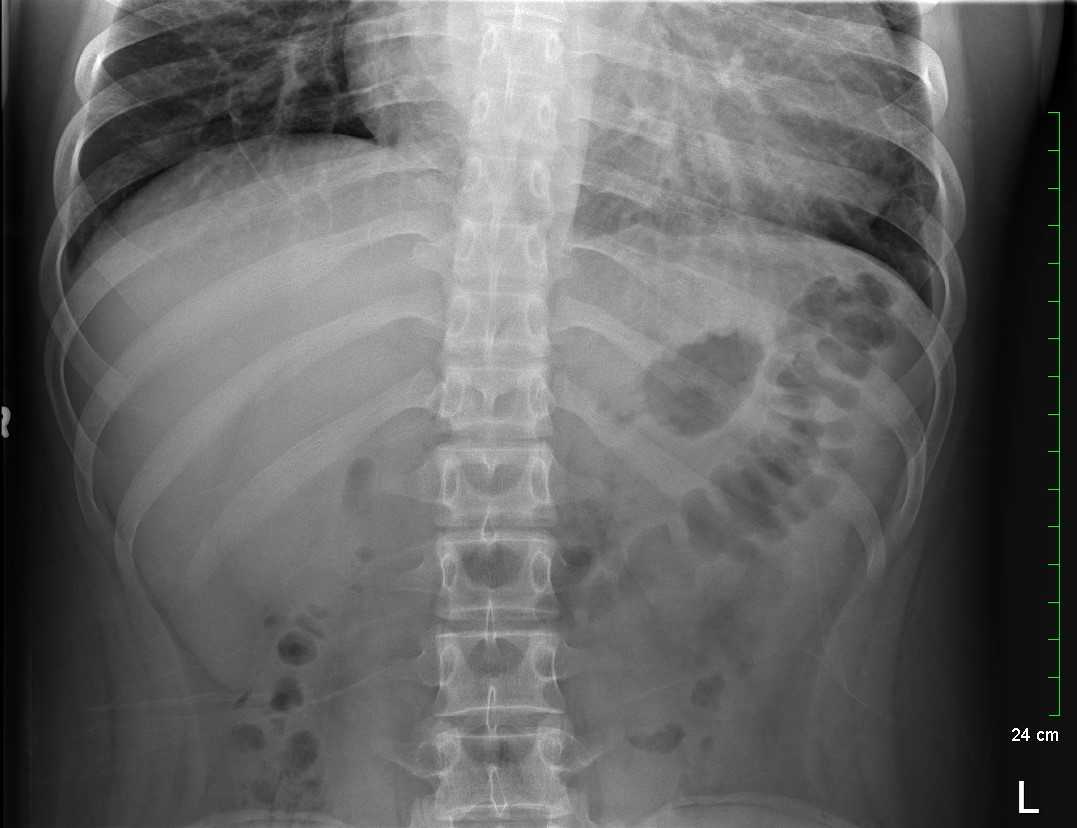

Because the patient presented with prolonged vomiting, a complete blood count (CBC), comprehensive metabolic panel (CMP), lipase, and kidney, ureter and bladder (KUB) was obtained. Initial labs showed only mild transaminitis and metabolic acidosis (AST 106, ALT 188, HCO3 15). KUB revealed the following images:

KUB read as normal by radiology. However, because of the enlarged heart border found incidentally on KUB, troponin I (0.05 ng/mL), B-type natriuretic peptide (BNP) (2186 pg/mL), and chest x-ray (CXR) was obtained, which showed the following: